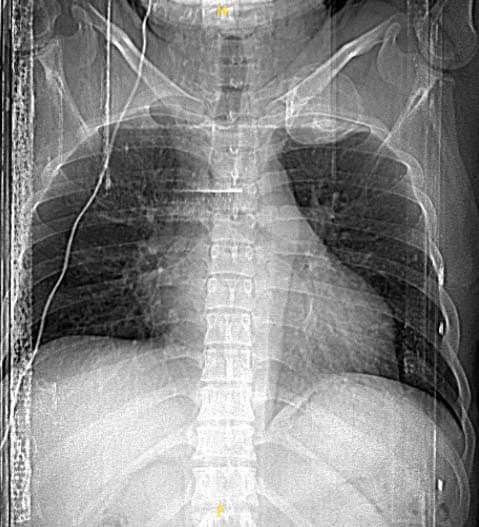

Bệnh nhân Hà Minh V. (nam, 33 tuổi, Cẩm Thủy, Thanh Hóa) đi khám vì đau tức nhẹ vùng vai trái khi vận động cánh tay kèm cảm giác tê bì nhẹ cánh tay trái, khám và chụp cắt lớp vi tính lồng ngực phát hiện u xương sườn kích thước lớn vị trí cung sau xương sườn số 1, u choán gần toàn bộ vùng hõm đỉnh.

Kết quả chụp cắt lớp vi tính ngực cho thấy hình ảnh khối u cung sau xương sườn số 1 kích thước 5x6cm, choán gần toàn bộ vùng hõm đỉnh bên trái, mặt trước của khối u dính sát phía sau động mạch, tĩnh mạch dưới đòn trái, bờ trên và sau của khối u nằm sát đám rối cánh tay, bờ dưới của khối u dính vào đỉnh phổi trái.

Nhận định về ca bệnh này, TS.BS Nguyễn Khắc Kiểm, Trưởng khoa Ngoại lồng ngực, Bệnh viện K chia sẻ: “Bệnh nhân có khối u xương kích thước lớn, tuy nhiên u nằm ở vị trí cung sau và chiếm toàn bộ xương sườn số 1, do vị trí giải phẫu xương sườn số 1 và cấu trúc liên quan (cơ, mạch máu, thần kinh) nên việc đưa ra phương án lựa chọn đường tiếp cận u, cắt u sao cho thuận lợi, triệt căn nhất và tránh được các tai biến như chảy máu, liệt cánh tay trái là vấn đề rất khó khăn.

Với tỷ lệ u xương tại xương sườn số 1 là rất hiếm gặp nên chưa có phương pháp phẫu thuật tiêu chuẩn nào được thiết lập. Với u xương lành tính nói chung, việc phẫu thuật là phương pháp điều trị triệt căn.

Đối với các u xương ở xương sườn số 1 là cực hiếm gặp, u to gây chèn ép vào bó mạch máu và đám rối thần kinh cánh tay sẽ gây ra các biến chứng nghiêm trọng như hội chứng lỗ thoát ngực. Chúng tôi đã hội chẩn, đưa ra nhiều phương án để cân nhắc kỹ càng sau đó tư vấn cho người bệnh”.